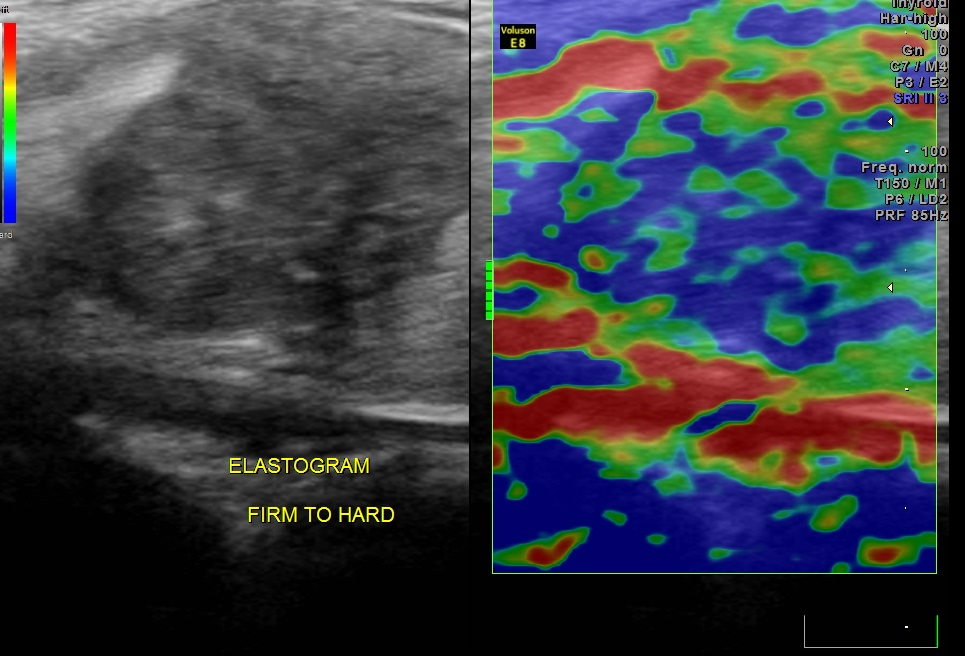

ELASTOGRAM of the mass revealed the consistency of the mass to be predominantly hard with some firm areas.